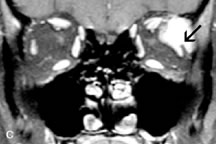

Application of a 90° RF pulse brings the excited nuclei into phase so that the net vector of their magnetic moments is directed perpendicular to the static magnetic field. Shortly thereafter, the magnetic moments of the nuclei spread out and point in different directions, leading to a loss of phase coherence and a resultant decay in signal intensity amplitude. The T2, or spin-spin relaxation time, is the rate of decrease in the signal of these excited nuclei as a result of the interaction and transfer of energy to unexcited adjacent nuclei. T2 ranges from a few milliseconds to a few hundred milliseconds and, for a given tissue, is always less than the Tl relaxation time. T2-weighted orbital images are easily recognized by a high-intensity signal from the vitreous (Fig. 9).5,8,16